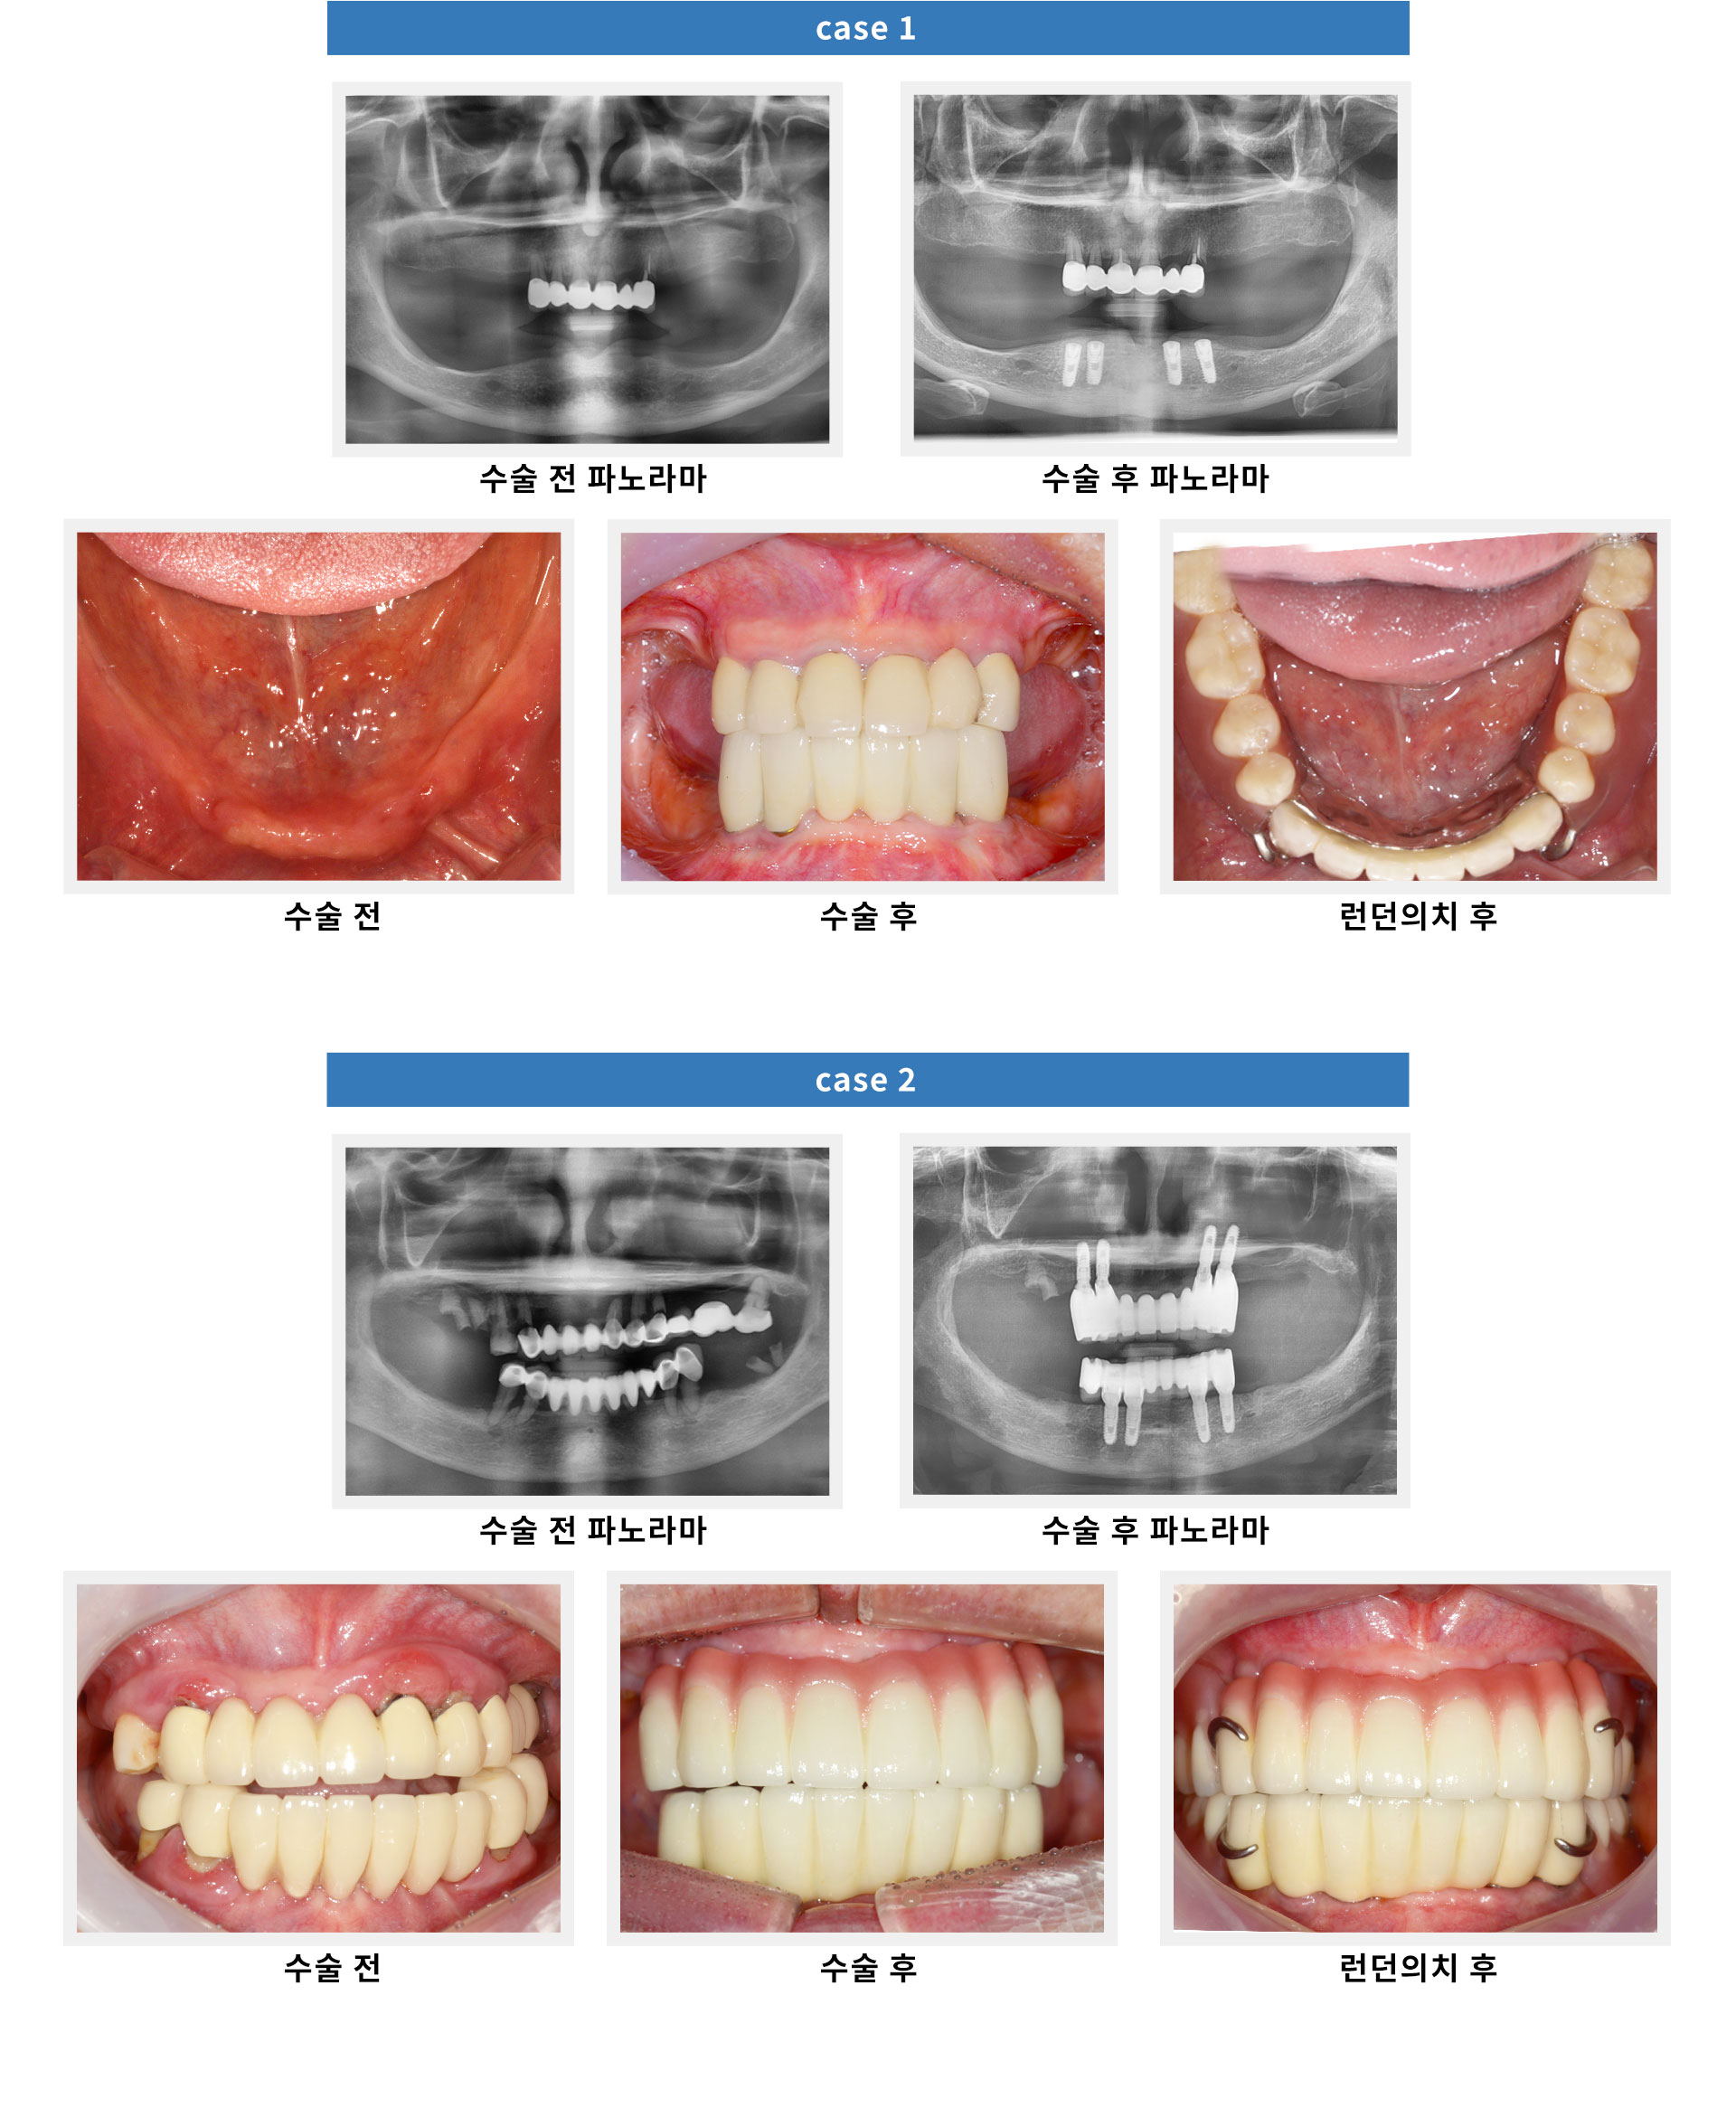

무치악 임플란트/틀니

전체치아 상실을 3~5회의 내원으로 해결하는

영국 런던대학의 특별한 기능인상법을 활용한 치료입니다.